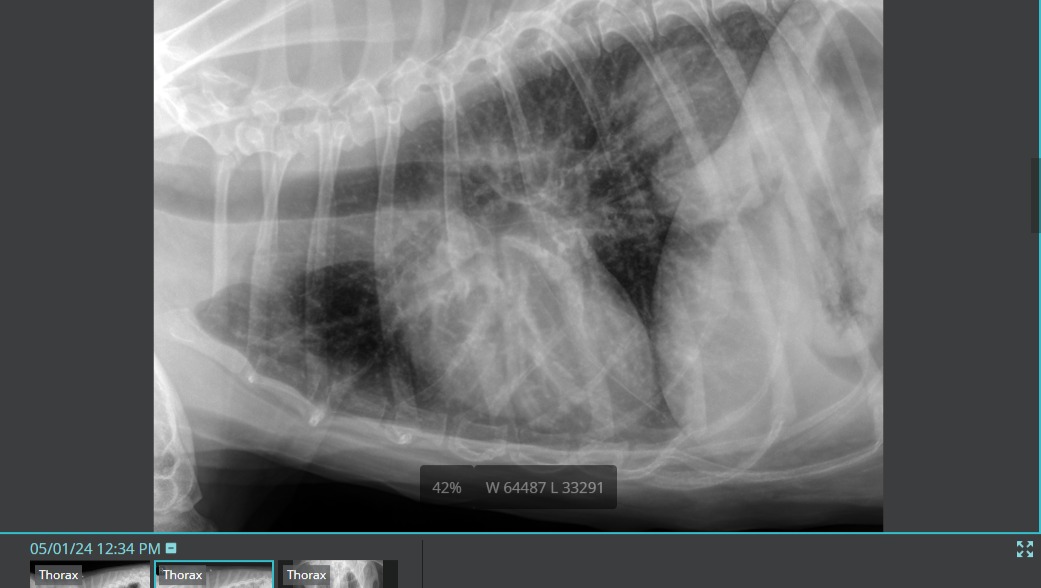

I was out of town for work for 11 days and picked Chewie up from his dog sitter this past Wednesday (5/1). He was extremely low energy and had a dry cough. I rushed him to the ER thinking he had pneumonia. After taking radiographs, we discovered that he has a very large tumor in his left lung. This tumor is so large that it is making it extremely difficult for Chewie to breathe, eat, go potty, and get comfortable resting.

This is an extremely aggressive cancer. He went from presenting zero symptoms to lethargy and trouble breathing within weeks. After lots of tests at the emergency vet, it was determined that Chewie only has the one isolated mass in his lung - that there are no other cancers present and all other organs are functioning normally.

Because the cancer is isolated to his left lung and his other organs still have full function, Chewie is a great candidate for a Lung Lobectomy - which will give him the chance for a full recovery, and give him several more years on this earth with us.